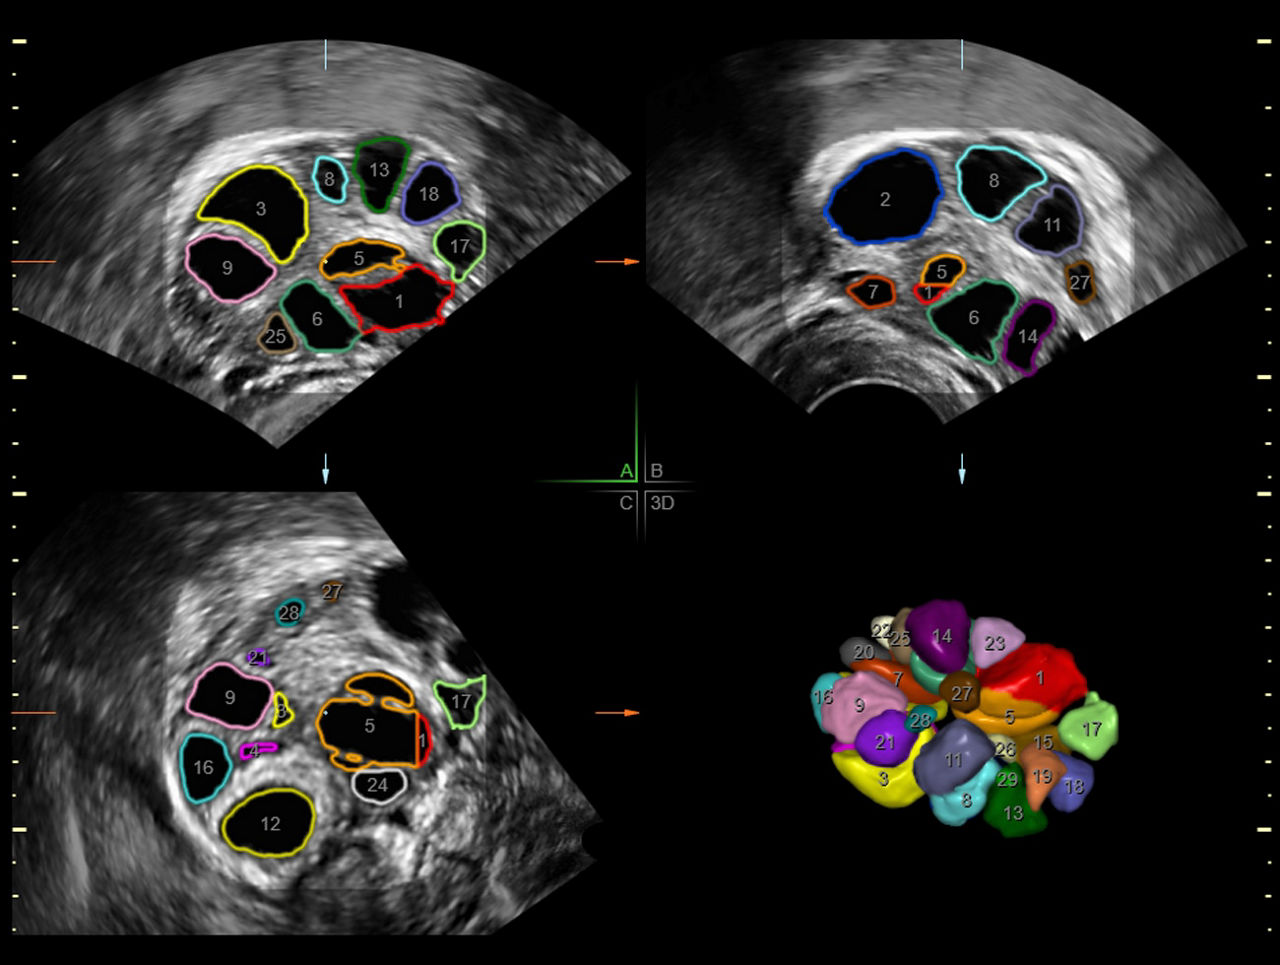

SonoAVC™follicle

SonoAVC™follicle automatically calculates the number, dimensions, and volume of hypoechoic structures in a volume sweep to help monitor patient follicles faster.